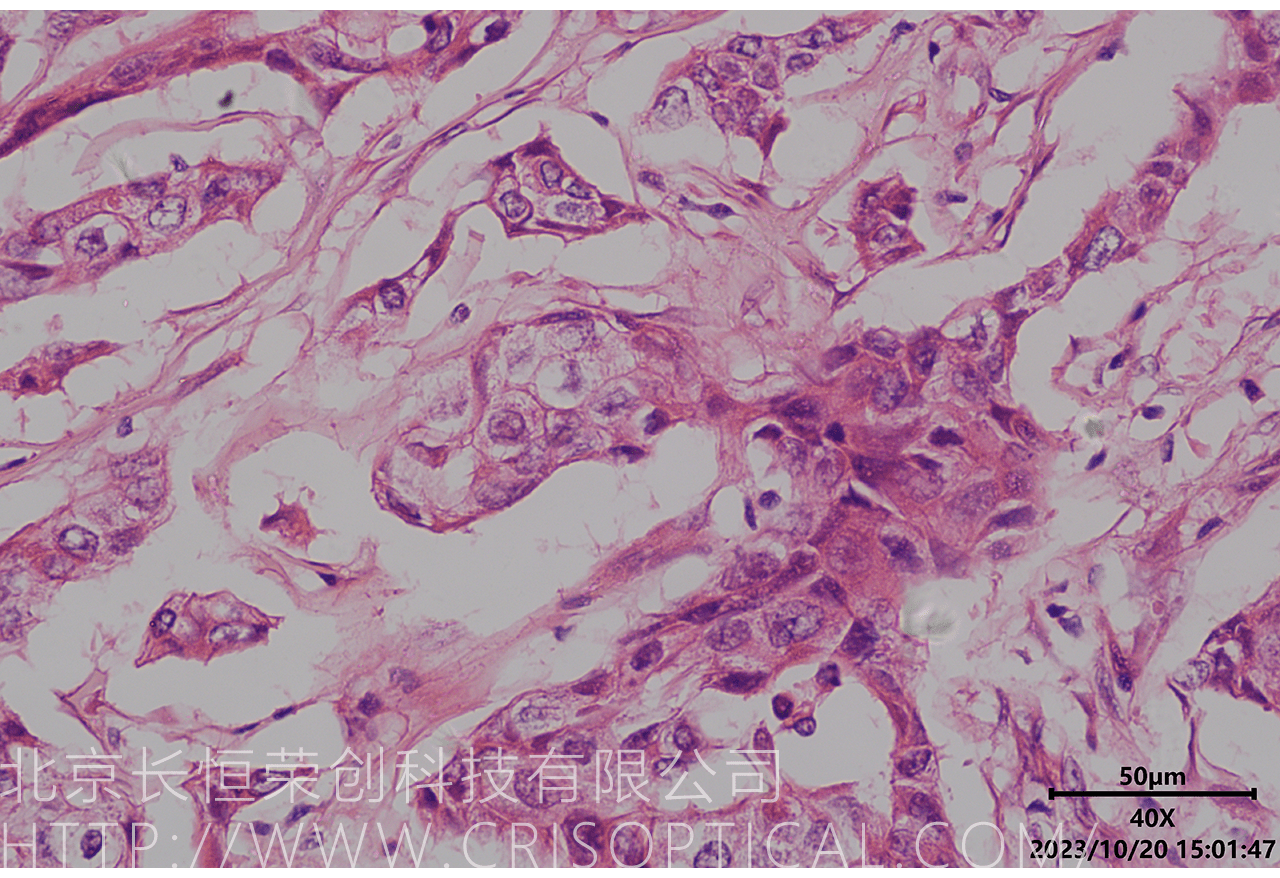

腫瘤診斷:對(duì)癌癥和其他腫瘤的病理切片觀察是確定腫瘤類型、分級(jí)和分期的關(guān)鍵步驟。醫(yī)生通過觀察組織樣本中的細(xì)胞形態(tài)、核形狀、分裂活性和其他特征,可以識(shí)別腫瘤的類型,幫助決定治療方法。